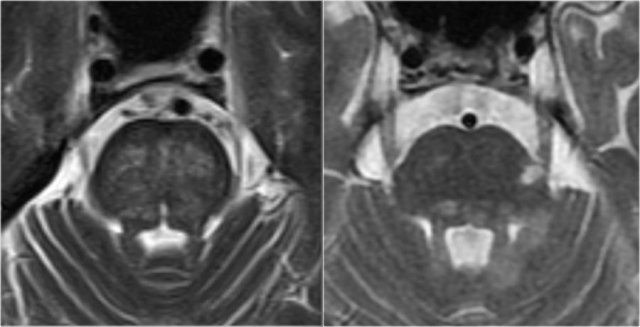

Here we see typical differences in vascular brainstem lesions compared to MS (same images as above).

The image on the left is an axial T2 weighted image illustrating typical vascular brainstem involvement, with a central involvement of the transverse pontine fibers.

The image on the right is an axial T2 weighted image of the brainstem of an MS-patient, showing typical peripherally located white matter lesions, often in or near the trigeminal tract, or bordering the 4th ventricle.